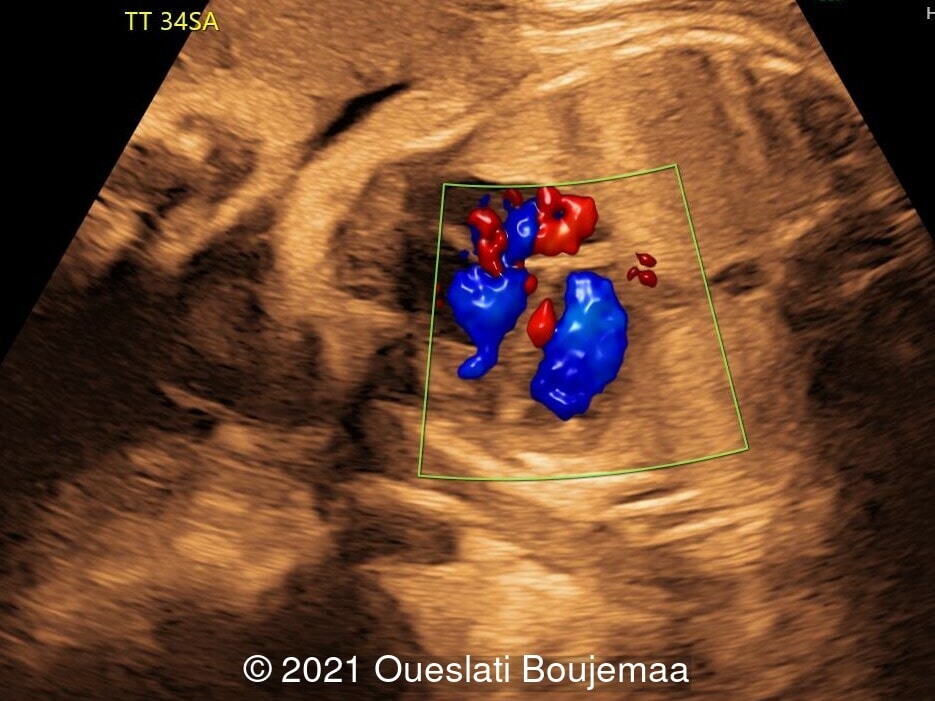

- Cardiac malformation with ventricular septal defect and linear insertion of the atrioventricular valves